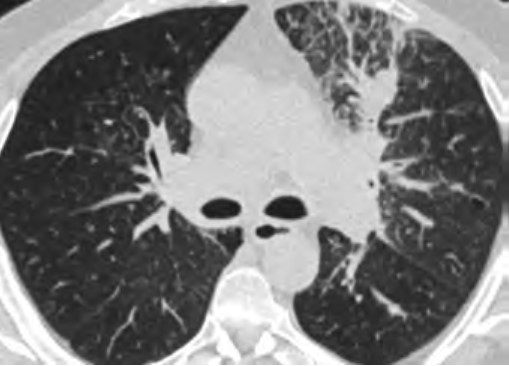

At the individual level, some of the barriers to awareness include unfamiliarity with LCS as a health preventive service tool (Fig. 2), unawareness of the new USPSTF and Centers for Medicare & Medicaid Services (CMS) recommendations for LCS, unfamiliarity with insurance coverage and costs, uncertainty about available accredited LCS programs, lack of culturally appropriate information, and lack of information at an appropriate health literacy level [8–10].